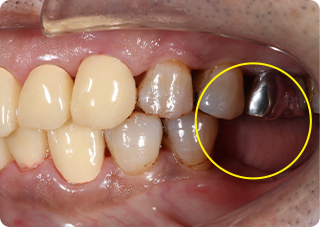

自家歯牙移植・精密根管治療・セラミッククラウン症例

術前

術後

| 主訴 | 奥歯の銀歯がぐらぐらして取れそう |

|---|---|

| 治療期間/回数 | 5ヵ月、10回 |

| 価格(税込) | 264,000円(税込) |

| リスク・副作用 | 生着不良、歯根吸収、骨性癒着の可能性 |

| ポイント | 銀歯の中でむし歯が進行し、保存不可能だったため抜歯し、後ろの親知らずを移植。移植の際に3Dプリンターで作製した親知らずのレプリカを使用し、治療時間の短縮と移植ポジションの確認を行った。生着するのを待ち、精密根管治療を行った後、セラミッククラウンを装着した。 |